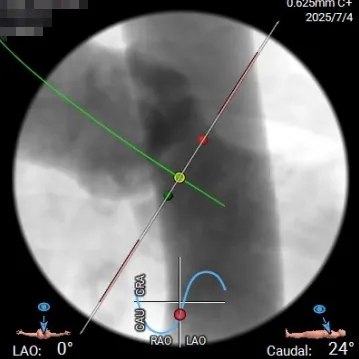

投照体位及瓣环角度分析

Angio

右窦中心

左右重合

右无重合-左冠切线位